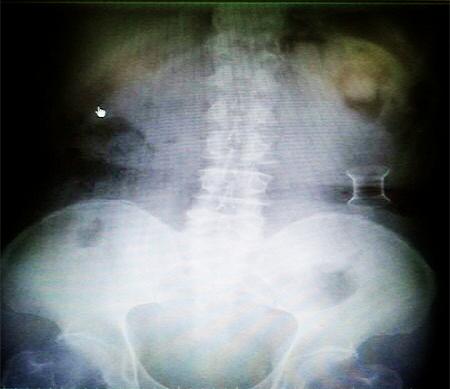

受試患者在結腸端端吻合術中,使用我司新研制產品達到了理想的預期效果?;颊咝g后7天、14天X光片顯影,可降解腸道支架均能按研制設計的預期時間節點保持應有強度,術后21天X光片顯示可降解腸道支架已完全破碎,并排出體外。在整個試驗過程中,病患無任何不良反映,耐受良好。